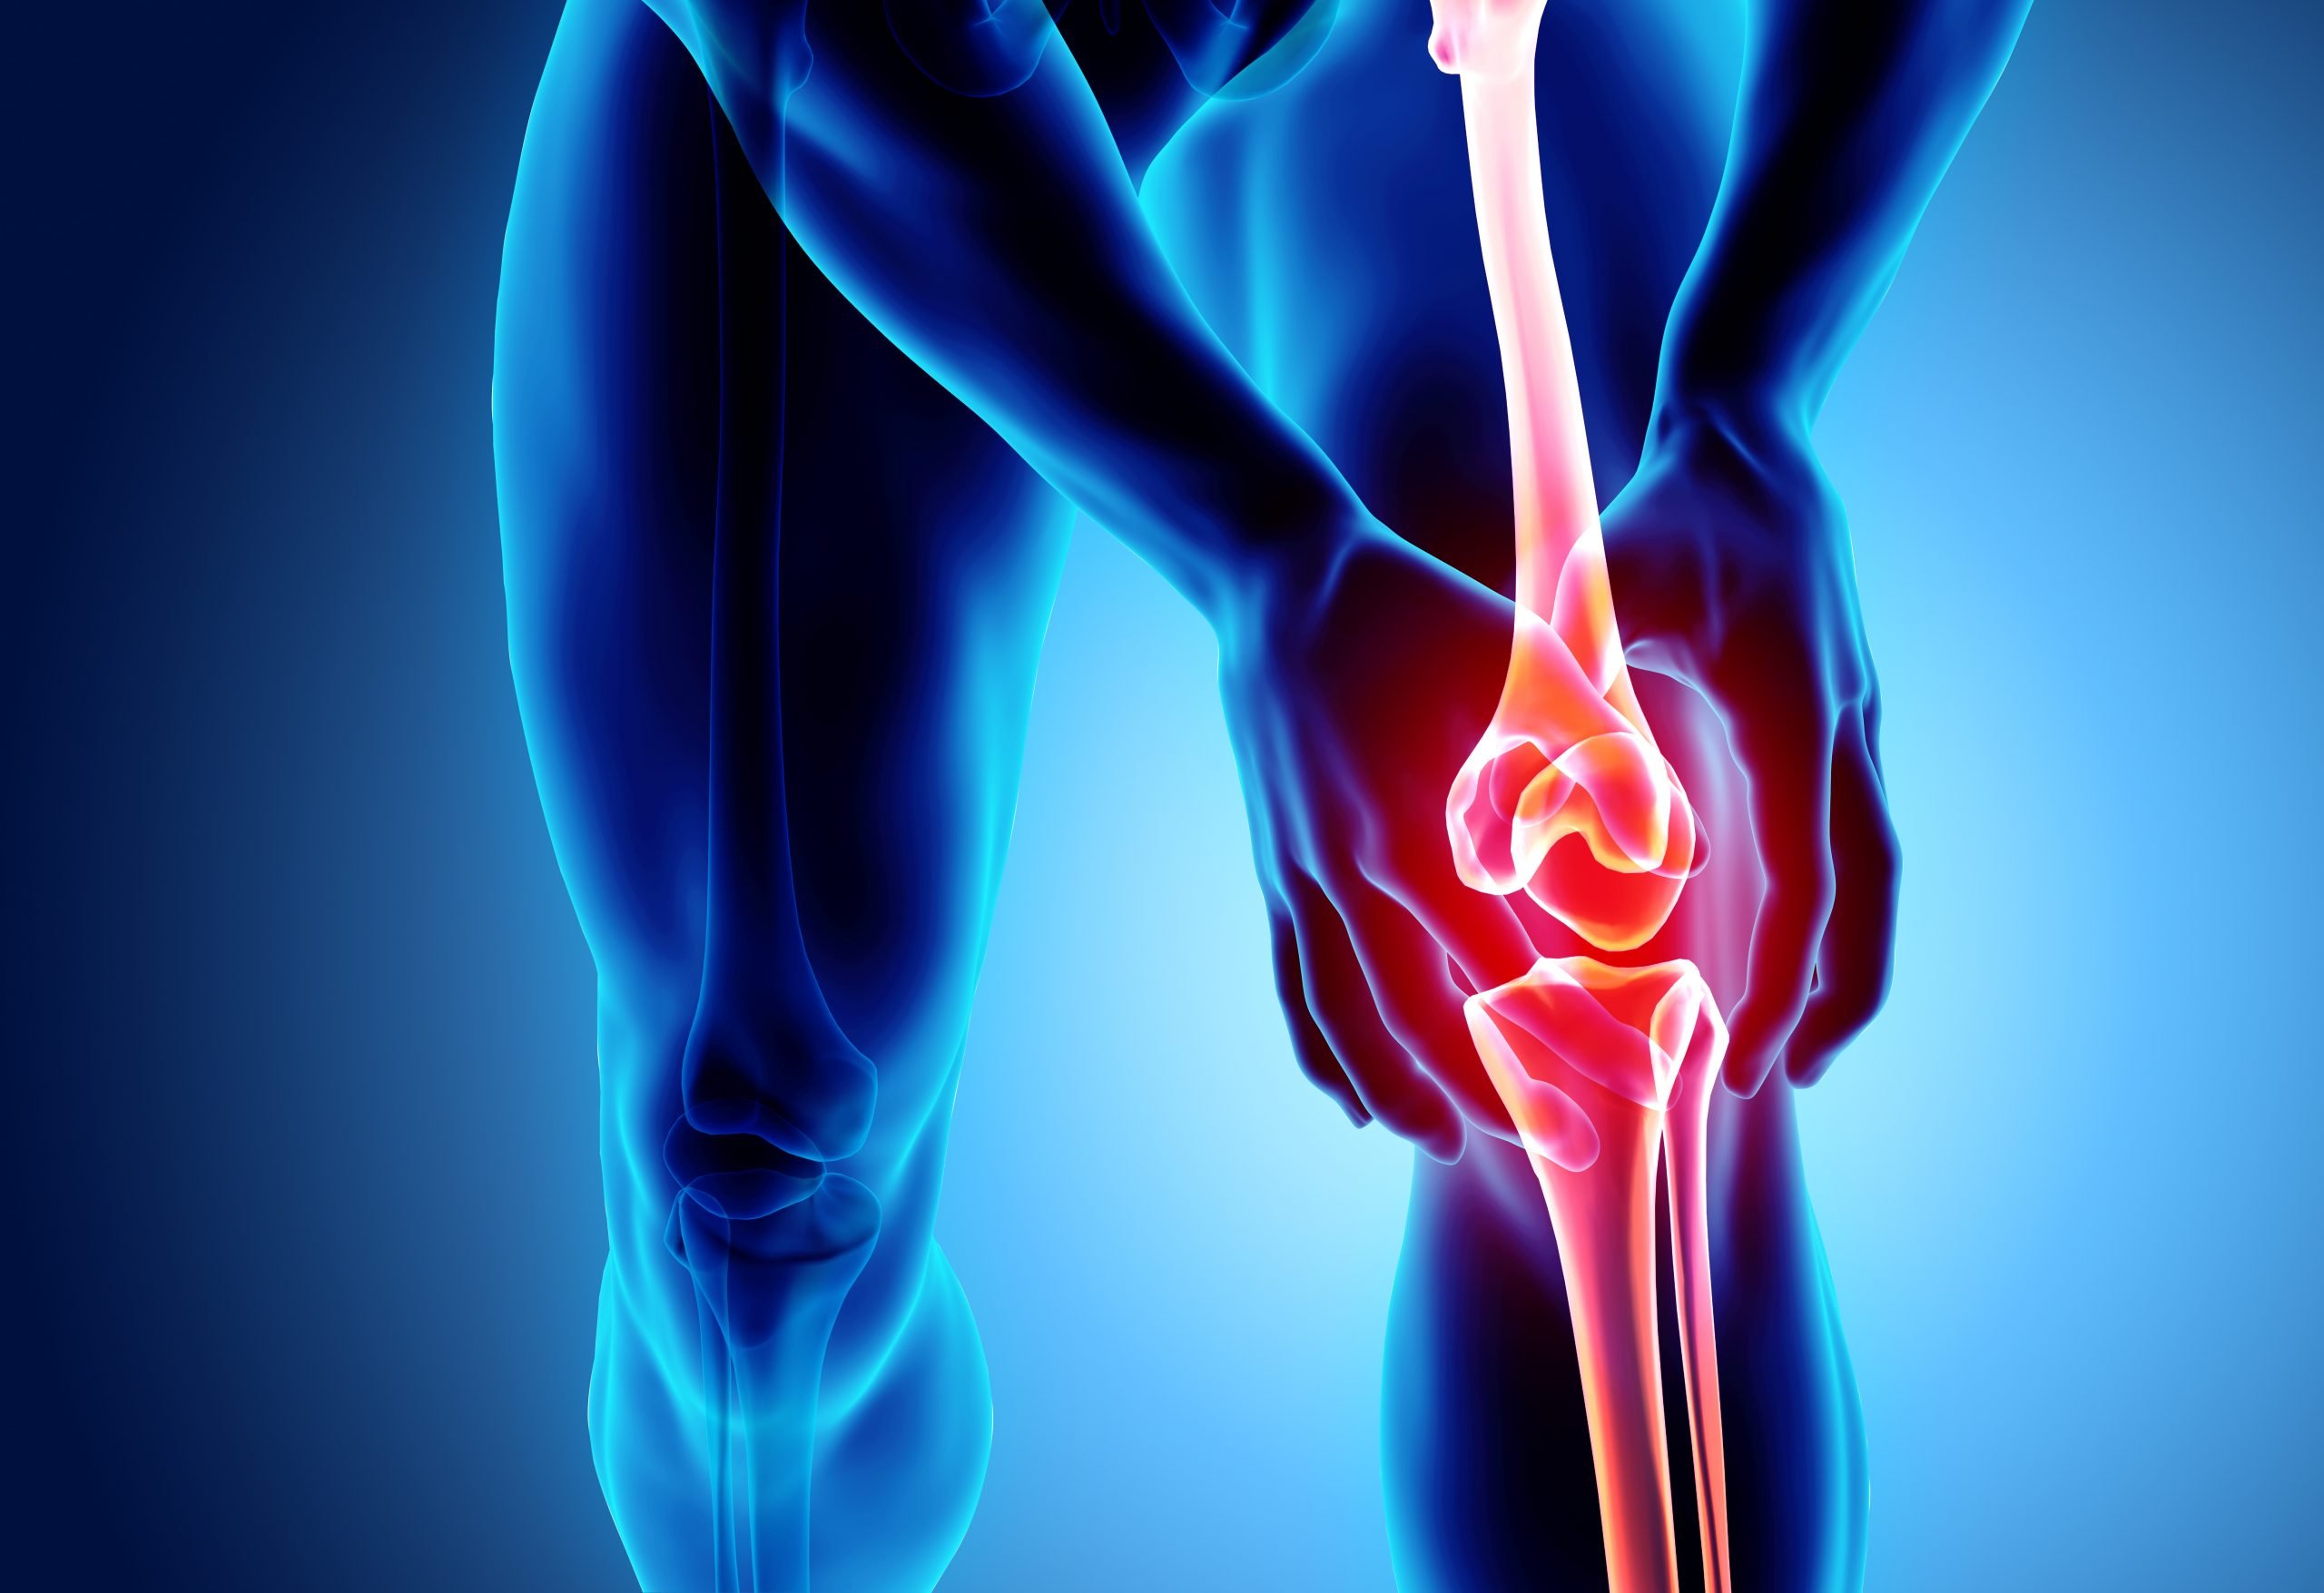

:max_bytes(150000):strip_icc()/knee-anatomy--artwork-452427829-599d8b9b22fa3a0011f2030d.jpg)